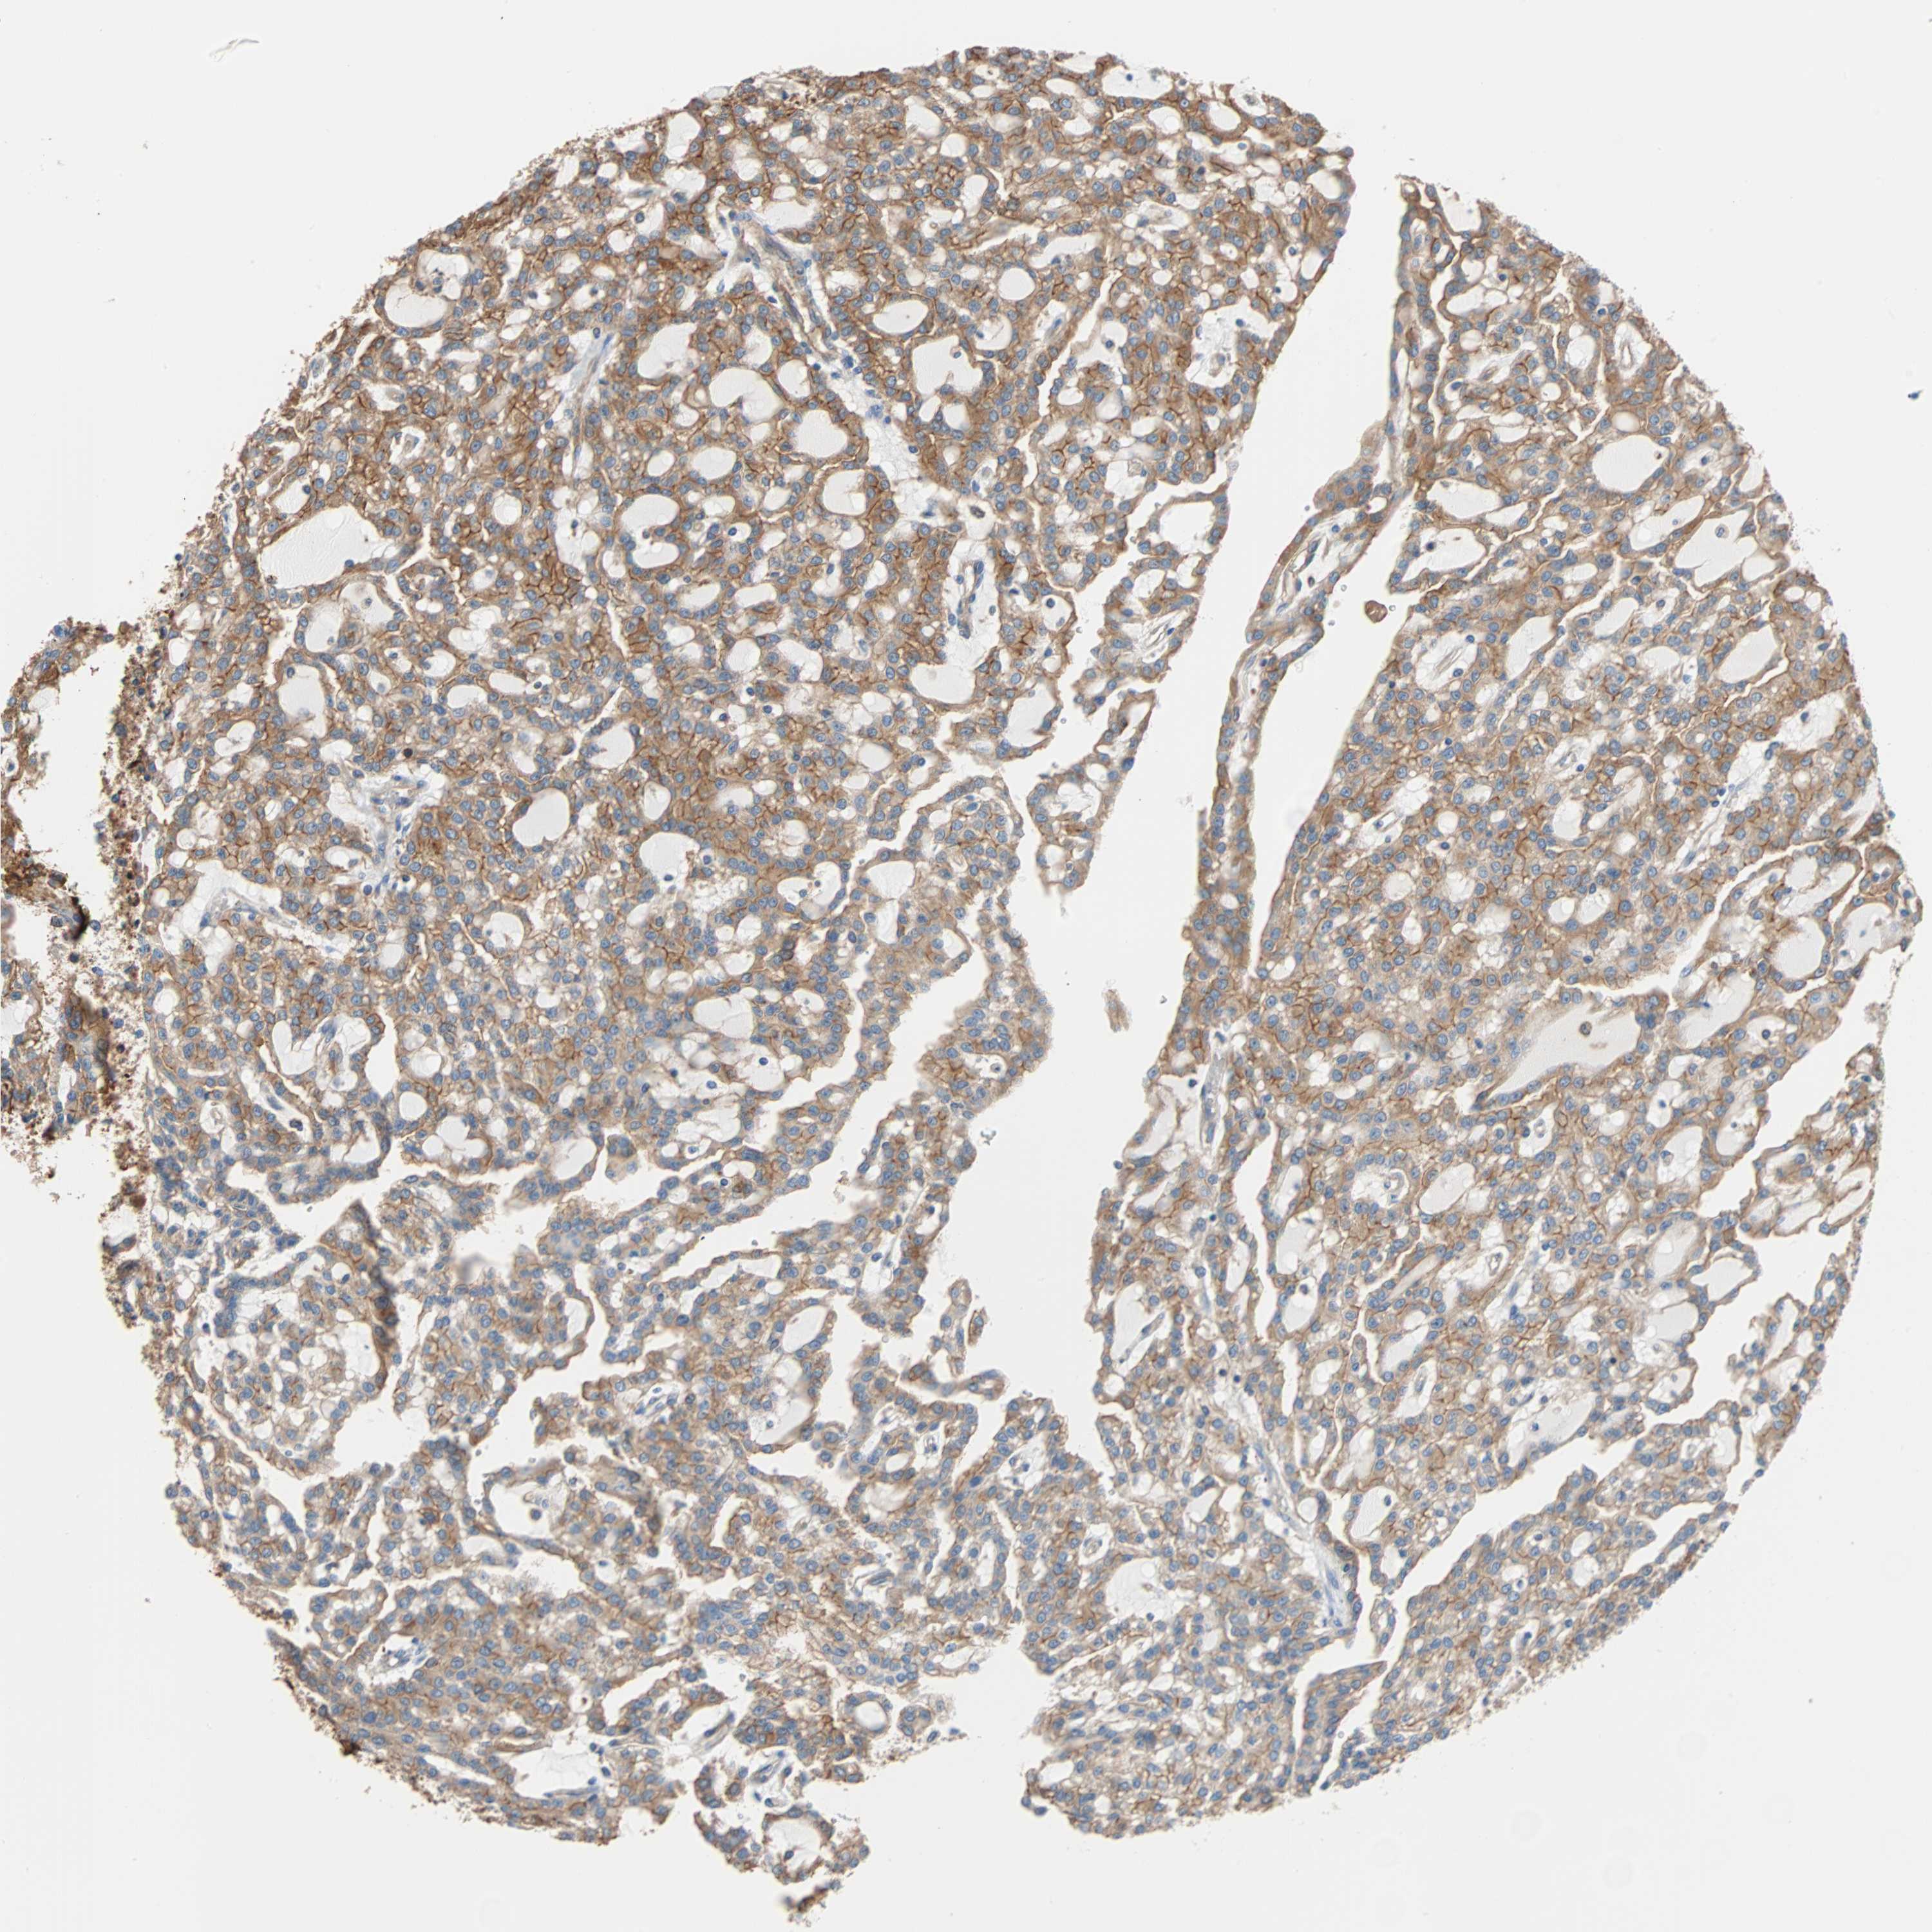

KIDNEY RENAL CLEAR CELL CARCINOMA (TCGA) - Interactive survival scatter ploti

The Survival Scatter plot shows the clinical status (i.e. dead or alive) for all individuals in the patient cohort, based on the same data that underlies the corresponding Kaplan-Meier plots. Patients that are alive at last time for follow-up are shown in blue and patients who have died during the study are shown in red.

The x-axis shows the expression levels (FPKM) of the investigated gene in the tumor tissue at the time of diagnosis. The y-axis shows the follow-up time after diagnosis (years). Both axes are complimented with kernel density curves demonstrating the data density over the axes. The top density plot shows the expression levels (FPKM) distribution among dead (red) and alive patients (blue). The right density plot shows the data density of the survived years of dead patients with high and low expression levels respectively, stratified using the cutoff indicated by the vertical dashed line through the Survival Scatter plot. This cutoff is automatically defined based on the FPKM cutoff that minimizes the p-score. The cutoff can be changed by dragging the vertical line or by entering a cutoff value in the square labeled "Current cut-off".

Under the Survival Scatter plot the p-score landscape (black curve; left axis) is shown together with dead median separation (red curve; right axis). Dead median separation is the difference in median mRNA expression between patients who have died with high and low expression, respectively. It is calculated as follows: median FPKM expression of dead patients with high expression - median FPKM expression of dead patients with low expression. This is intended to aid the user in visually exploring custom cutoffs and the associated p-scores and dead median separation.

Individual patient data is displayed and can be filtered by clicking on one or more of the category buttons on the top of the page. Categories describing expression level and patient information include: high, low, alive, dead, female, male and tumor stages. The scale of the x-axis can be toggled between linear and log-scale by clicking on the "x log" button. Mouse-over function shows TCGA ID, patient information and mRNA expression (FPKM) for each patient.

& Survival analysisi

Kaplan-Meier plots summarize results from analysis of correlation between mRNA expression level and patient survival. Patients were divided based on level of expression into one of the two groups "low" (under cut off) or "high" (over cut off). X-axis shows time for survival (years) and y-axis shows the probability of survival, where 1.0 corresponds to 100 percent.

EEF2 is potential prognostic, high expression is favorable in Kidney Renal Clear Cell Carcinoma (TCGA)

Best expression cut offi

Based on the FPKM value of each gene, patients were classified into two groups and association between prognosis (survival) and gene expression (FPKM) was examined. The best expression cut-off refers the FPKM value that yields maximal difference with regard to survival between the two groups at the lowest log-rank P-value. Best expression cut-off was selected based on survival analysis .

When clicking on this number, the vertical dashed line indicating cut-off, the interactive survival plot, and the Kaplan-Meier curve will be adjusted to show results based on the best expression cut-off.

: 1069.53

TCGA RNA samplesi

RNA-seq data is reported as average FPKM (number Fragments Per Kilobase of exon per Million reads), generated by the The Cancer Genome Atlas (TCGA) .

Normal distribution across the dataset is visualized with box plots, shown as median and 25th and 75th percentiles. Points are displayed as outliers if they are above or below 1.5 times the interquartile range. FPKM values of the individual samples are presented next to the box plot.

Average pTPM 1352.9

Number of samples 521